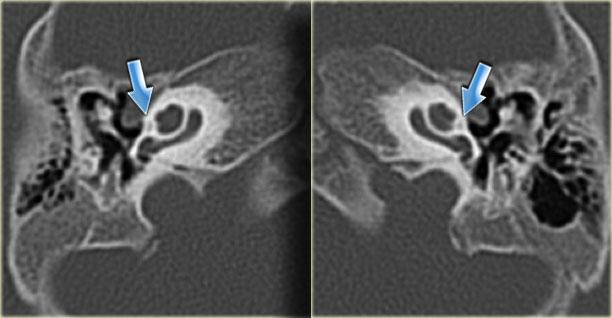

Bên trái là hình ảnh cắt ngang và cắt vành của một bệnh nhân nam 64 tuổi.

Hành tĩnh mạch cảnh nhô lên cao hơn bờ dưới của ống bán khuyên sau (mũi tên).

Hành tĩnh mạch cảnh thường không đối xứng, với hành tĩnh mạch cảnh bên phải thường lớn hơn bên trái.

Khi hành tĩnh mạch cảnh vượt lên trên ống bán khuyên sau, được gọi là hành tĩnh mạch cảnh cao.

Khi vách xương ngăn cách giữa hành tĩnh mạch cảnh và hòm nhĩ bị khuyết, được gọi là hành tĩnh mạch cảnh hở.

Hiếm gặp hơn là hình ảnh túi phình nhỏ – được gọi là túi thừa hành tĩnh mạch cảnh.

Túi thừa hành tĩnh mạch cảnh

Bên trái là hình ảnh cắt ngang và cắt vành của một bệnh nhân nam 50 tuổi.

Phát hiện tình cờ túi thừa hành tĩnh mạch cảnh (mũi tên).